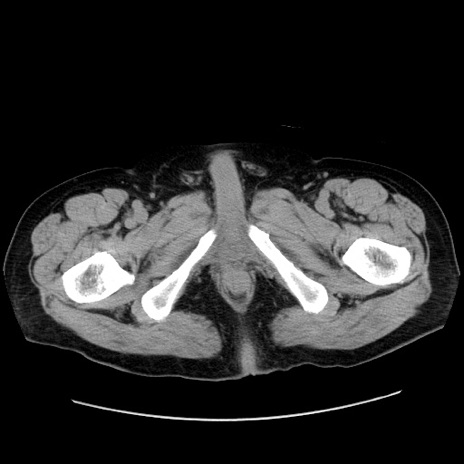

症例30(横断像)

【症例】80歳代男性

【主訴】臍周囲痛

【現病歴】約6時間前から臍下部痛が出現。次第に腹部膨隆・背部痛も生じてきたため来院。背部痛の場所は変化しない。

【身体所見】意識清明、BT 36.3℃、BP  131/87mmHg、P 87bpm、SpO2 100%(RA)、臍周囲自発痛・圧痛あり、反跳痛なし、自発痛部位に一致して板状硬あり、腹部膨隆、腸雑音減弱、CVA tenderness両側陰性。